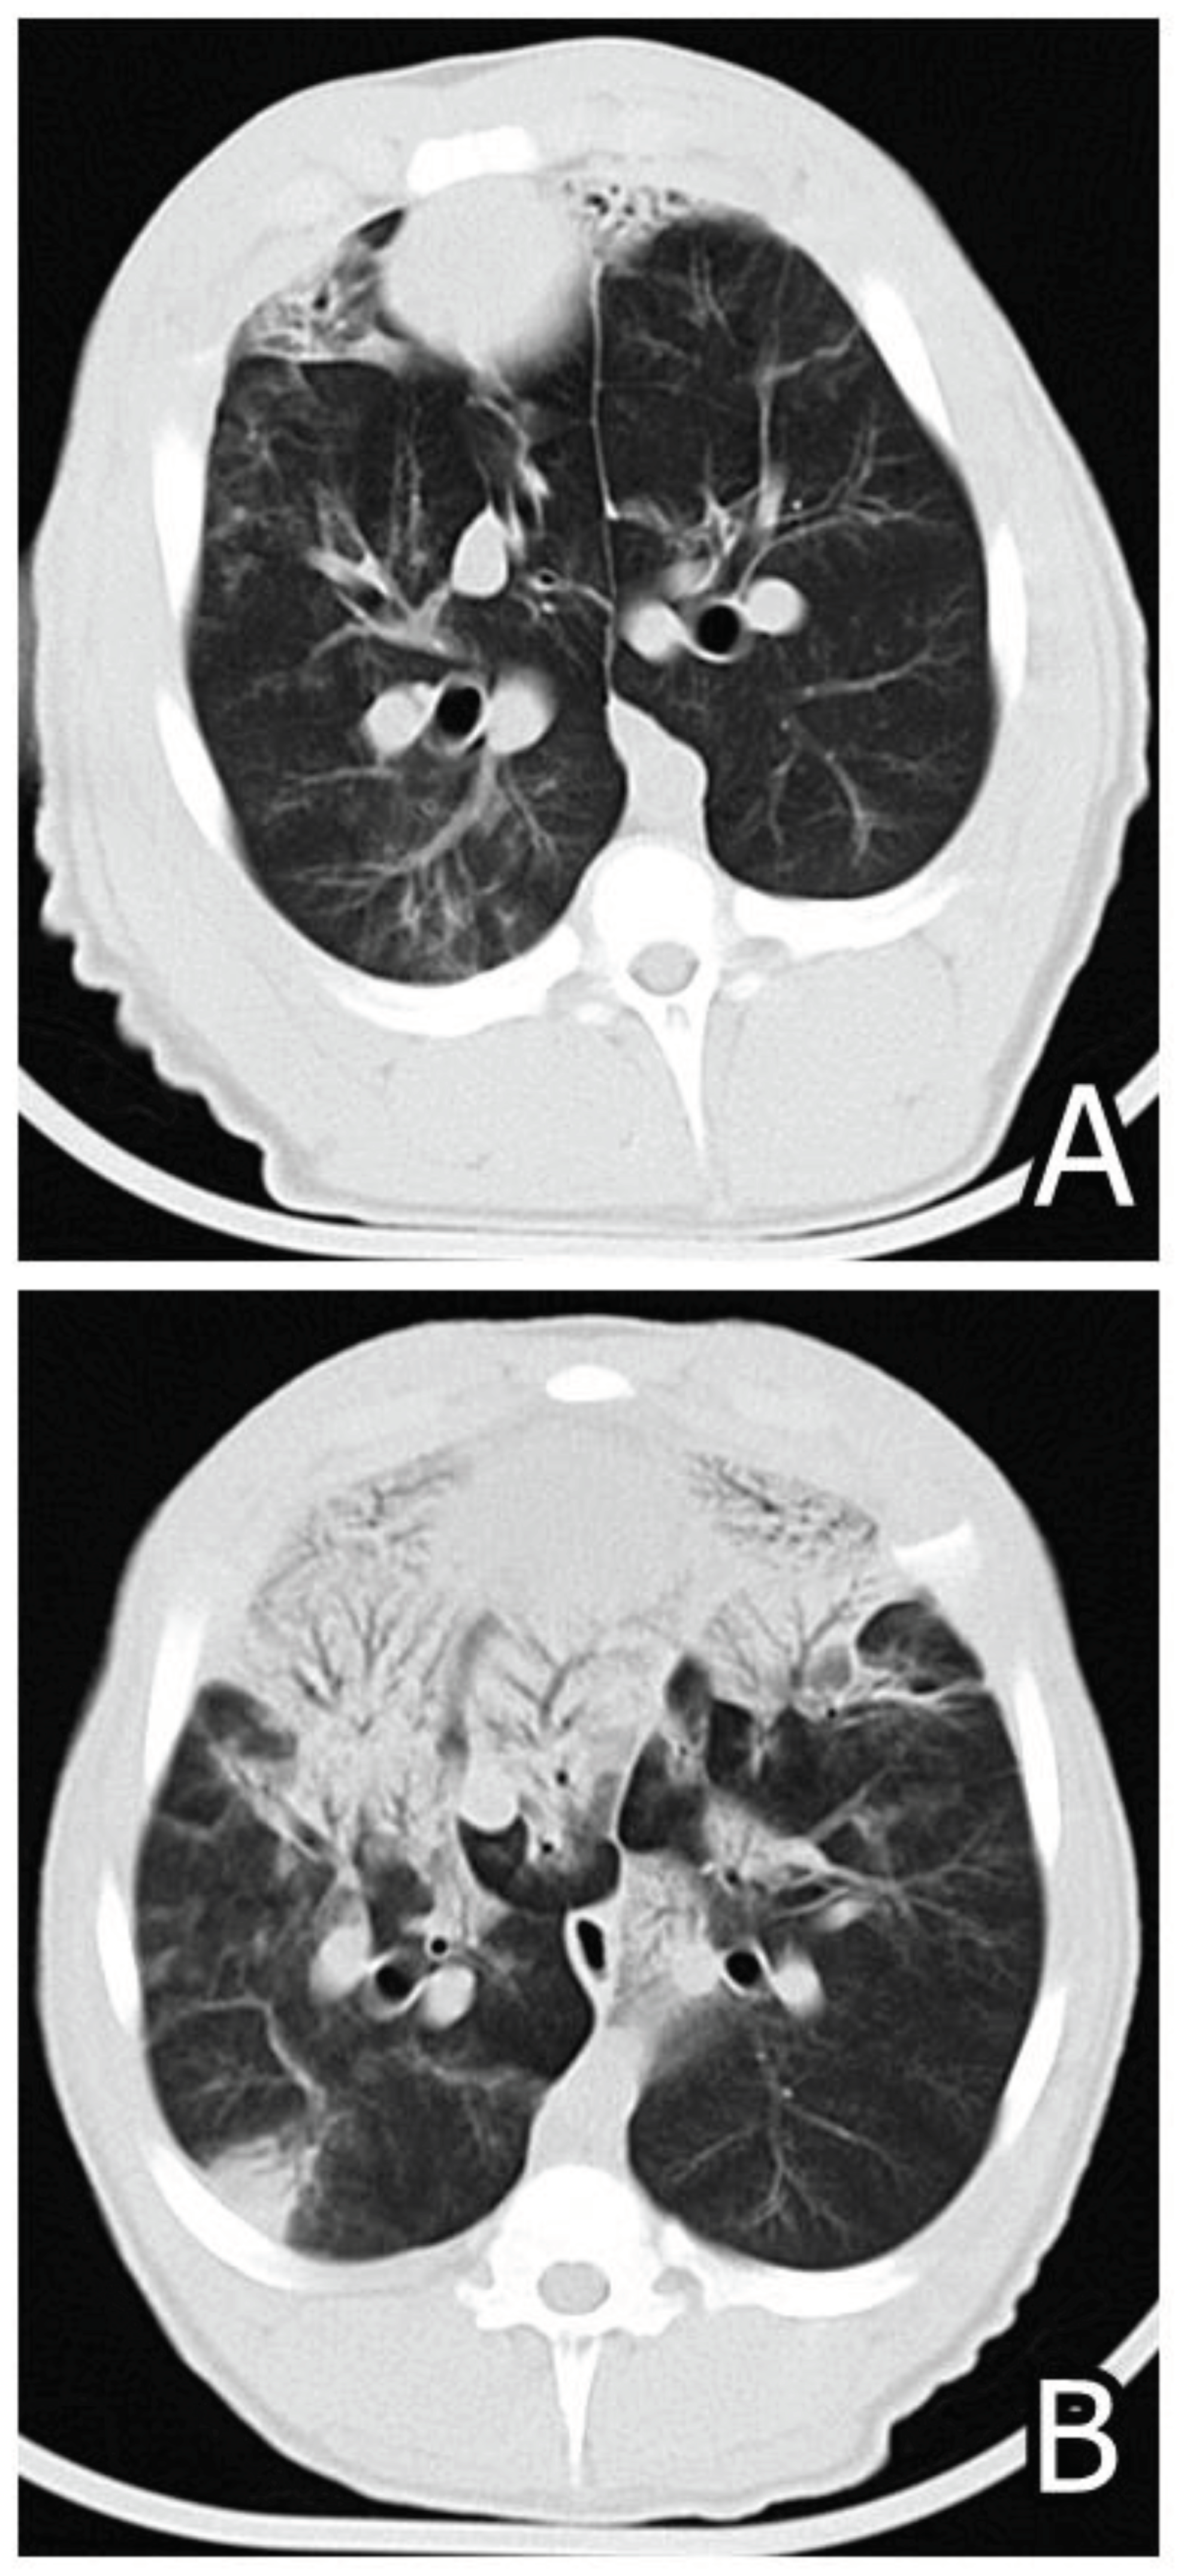

- Pósa, R., Donkó, T., Bogner, P., Kovács, M., Repa, I., Magyar, T. (2011). Interaction of Bordetella bronchiseptica, Pasteurella multocida and fumonisin B1 in the porcine respiratory tract followed up by computed tomography. Can. J. Vet. Res., 75, 176-183.

- Pósa, R., Magyar, T., Stoev, S.D., Glávits, R., Donkó, T., Repa, I., Kovács, M. (2013). Use of Computed Tomography and Histopathologic Review for Lung Lesions Produced by the Interaction Between Mycoplasma hyopneumoniae and Fumonisin Mycotoxins in Pigs. Vet. Pathol., 50(6), 971-979.

- Pósa, R., Stoev, S.D., Kovács, M., Donkó, T., Repa, I., Magyar, T. (2016). A comparative pathological finding in pigs exposed to fumonisin B1 and/or Mycoplasma hyopneumoniae, Tox. Ind. Health, 32, 6, 998-1012.